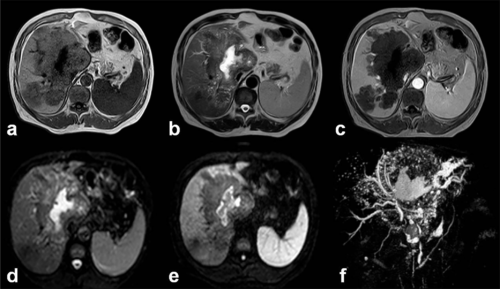

Ехографията и КАТ имат голяма диагностична стойност за обективизиране на съобщението. Добре е в някои случаи да бъдат извършени рентгенографски на корема и гръдния кош, с цялата по-голяма яснота по отношение на показаното, локализация, отношения с околни структури, изясняване на хирургичния достъп и др.